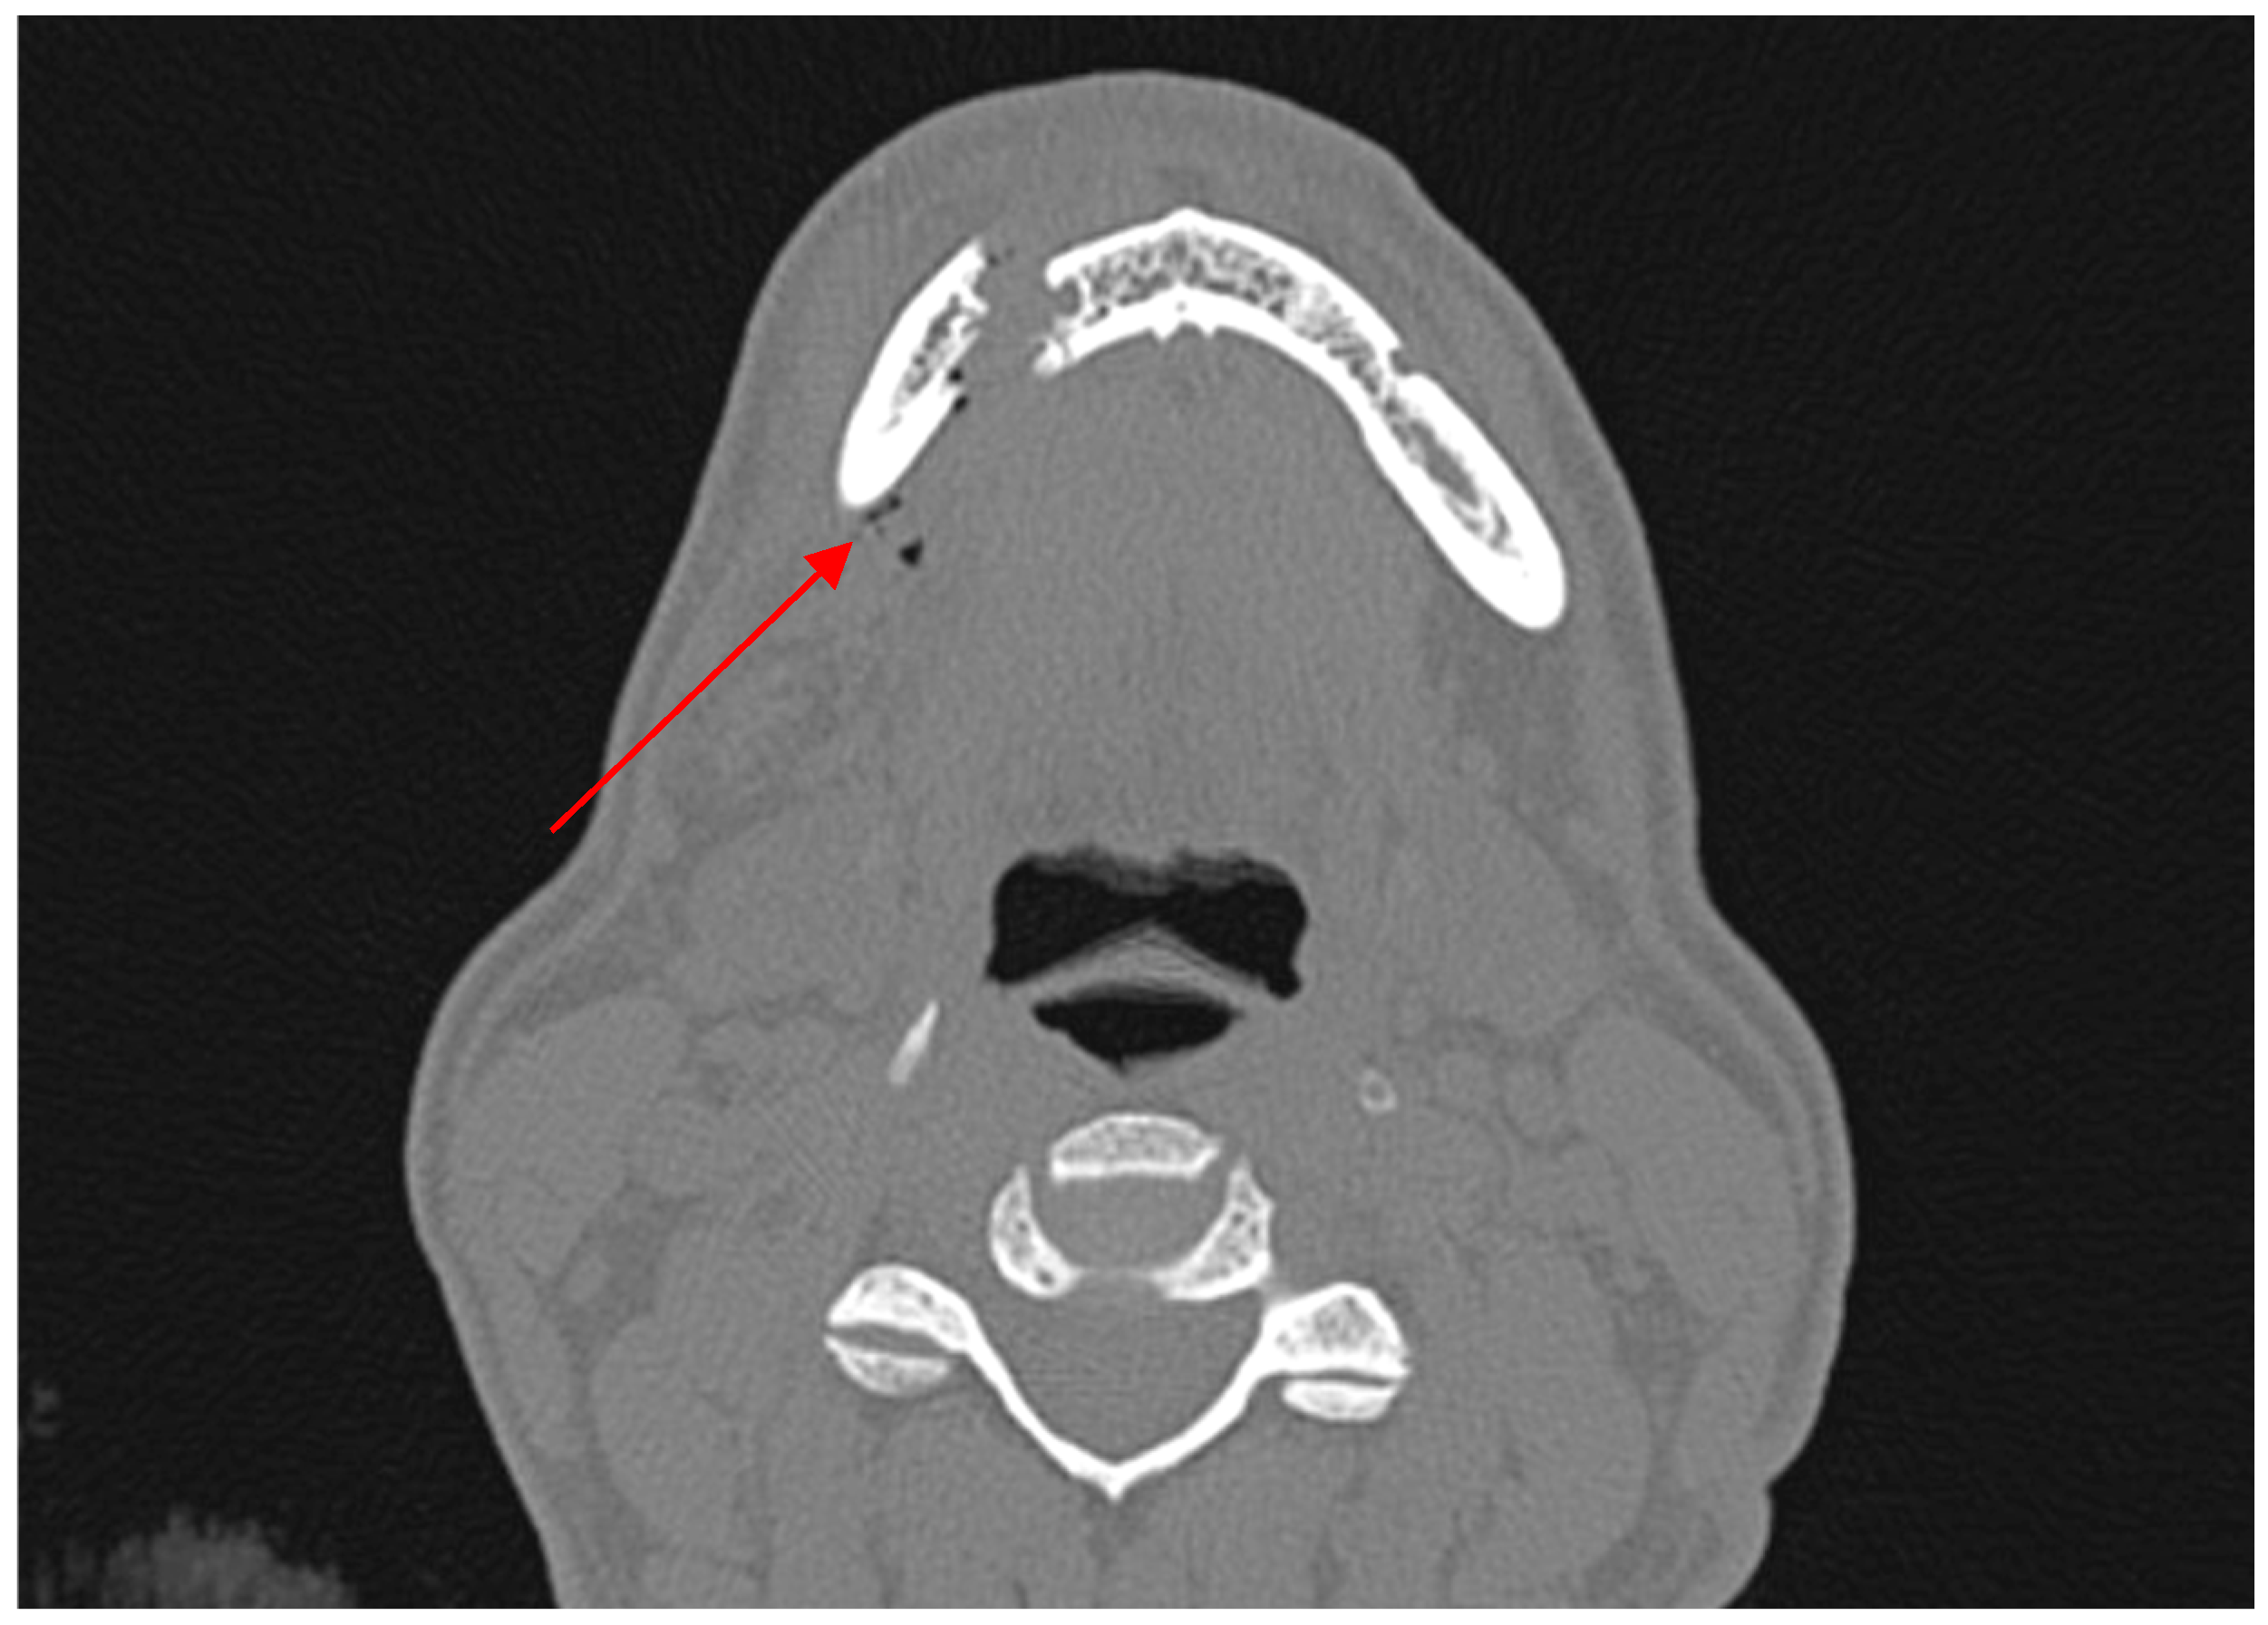

- True positive (TP)—diagnosed body/angle fracture + presence of AS in soft tissues.